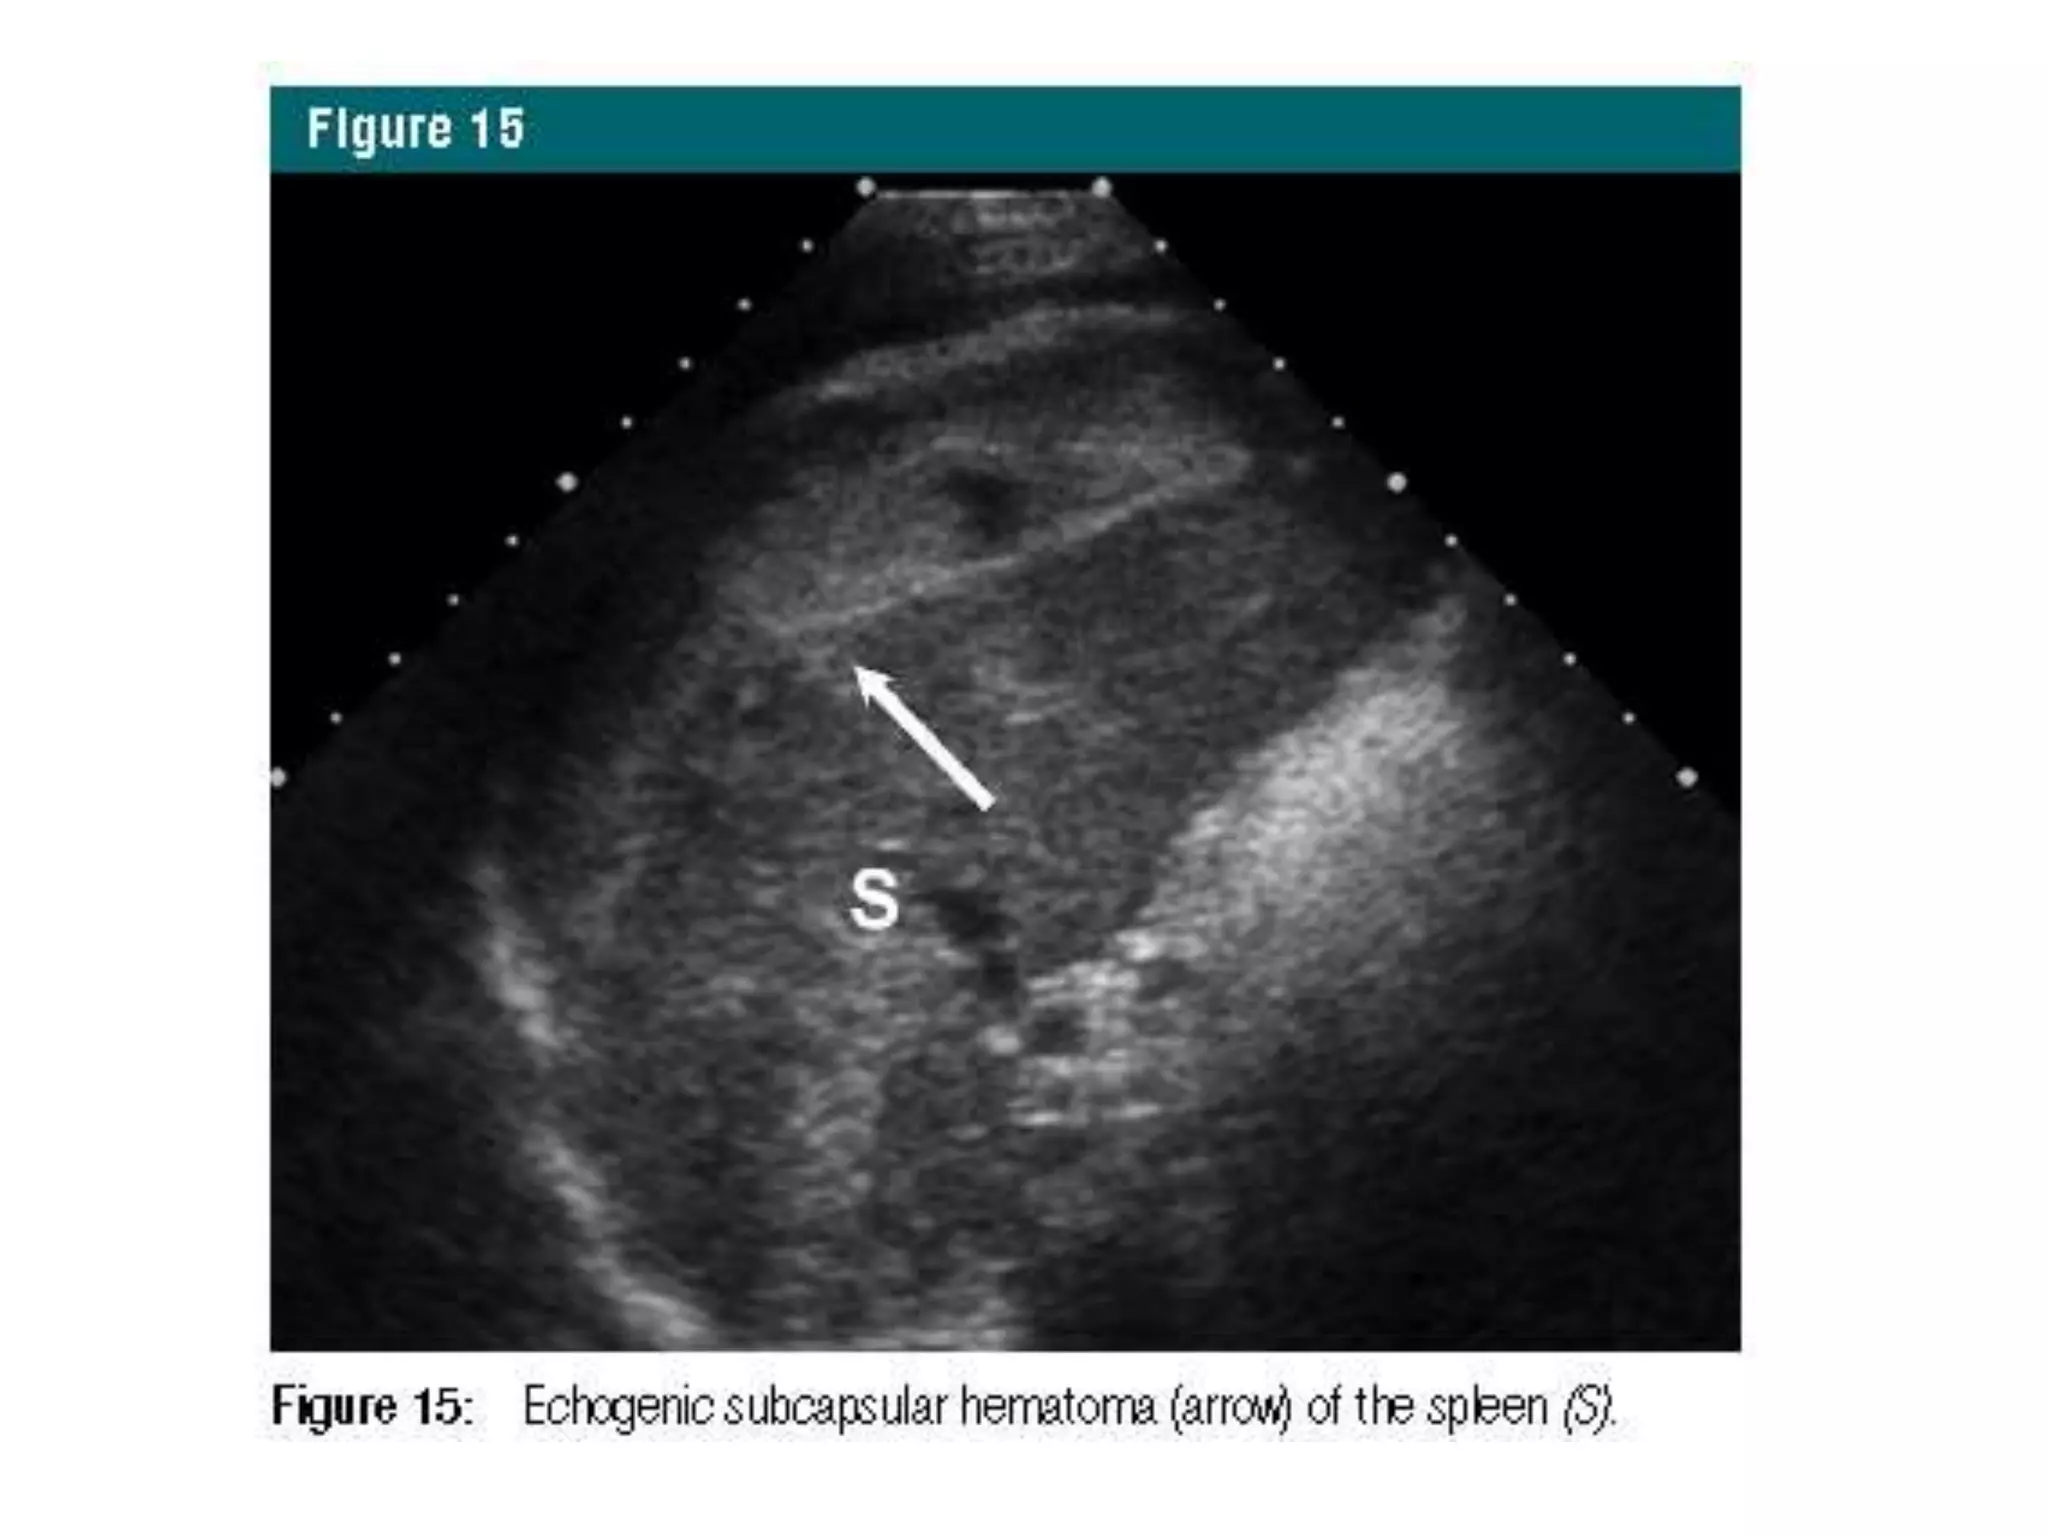

Solid Organ Evaluation

• well suited to depict abnormalities indicative of injury

• diffuse heterogeneous pattern  splenic lacerations

• discrete hyperechoic pattern  hepatic lacerations .

• Subcapsular splenic hematomas - hyperechoic or

hypoechoic rims surrounding the parenchyma and

• splenic lacerations - hypoechoic over a few days.

Solid Organ Evaluation •well suited to depict abnormalities indicative of injury • diffuse heterogeneous pattern  splenic lacerations • discrete hyperechoic pattern  hepatic lacerations . • Subcapsular splenic hematomas - hyperechoic or hypoechoic rims surrounding the parenchyma and • splenic lacerations - hypoechoic over a few days. • For urological trauma, – high-grade renal injuries - mixed echogenicity with a disorganized pattern, and – bladder hematomas frequently appear echogenic